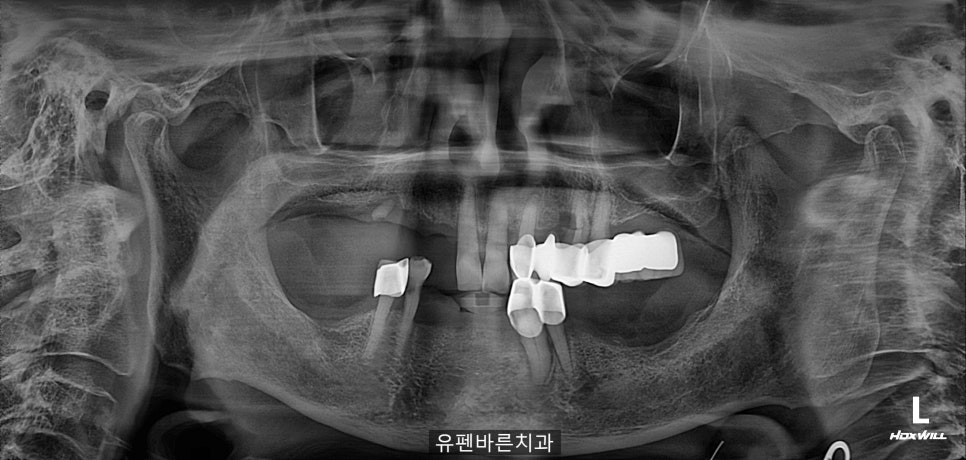

엑스레이 촬영 결과

교합이 맞지 않고,

왼쪽위의 브릿지는

흔들거리고

치아들이 정출되어

위 앞니가 내려와

아래 잇몸에 닿고 있는

상태셨어요,,,

10개월에 걸쳐 진행된

임플란트

수술인 만큼